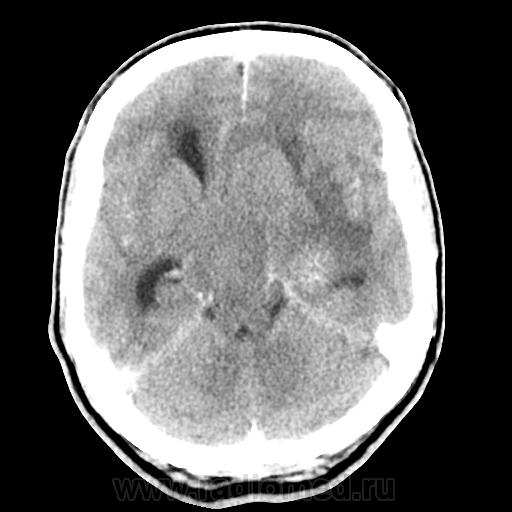

КТ ГМ+С Объемное образование левой гемисферы большого мозга. Внутрижелудочковая менингиома?

Мужчина 66 лет. Поступил с подозрением на ОНМК. Жалобы на атаксию и когнитивные нарушения (родственники рассказали о его плохой памяти, рассеянности, забывчивости, в последнее время, а также о нарушении речи и невнятности в произношении "мямлил"). Объемное образование в теменной, височной доли и базальных ядрах слева. Вазогенный отек. Выраженный масс-эффект. Латеральная дислокация вправо на 1,5см. Не могу дифференцировать интравентрикулярно ли, субэпендимарно ли расположено или за счет такого масс-эффекта? Ипсилатеральный желудочек компремирован, контрлатеральный компенсаторно расширен, височные рога боковых желудочков расширены, III желудочек значительно сужен и не дифференцируется, IVинтактен. Сильвиев водопровод сужен, достоверно не дифференцируется, супраселлярная цистерна сужена. Субарахноидальные борозды и конвекситальные пространства сужены. Выраженно диффузно очень интенсивно накапливает КВ. DDs: более вероятно: менингиома,  менее вероятно: субэпендимарная АСЦ, анапластическая АСЦ, глиобластома. Сложилось впечатление с большей вероятностью о внутрижелудочковой менингиоме с экстравентрикулярным ростом.